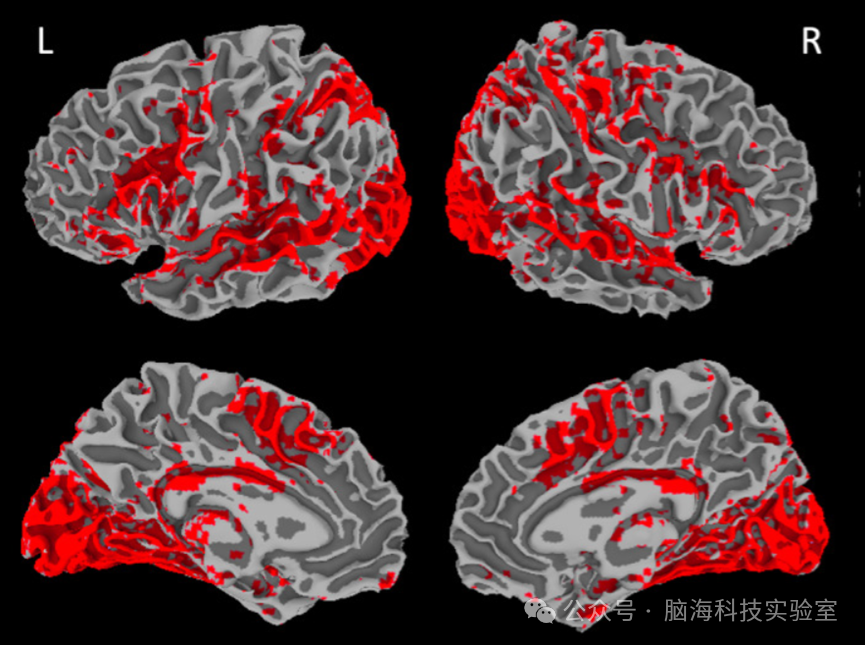

图1 L1英语和L2普通话显著激活的区域(p = 0.01)未校正。 结果叠加在MNI空间的立体定向脑上。L =左,R =右